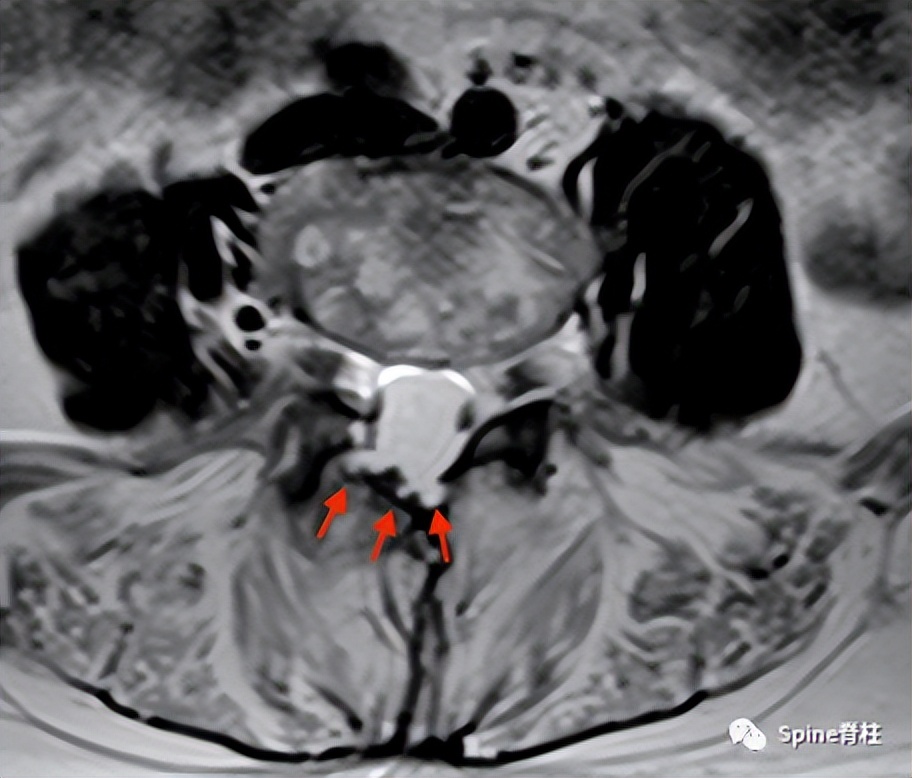

强直性脊柱炎患者L4-5水平的横断面T2(上图)和矢状位T2(下图)加权像提示多发性蛛网膜憩室(arachnoid diverticula)以及椎板和棘突的侵蚀(红色箭头),但需注意憩室周围的神经根粘连